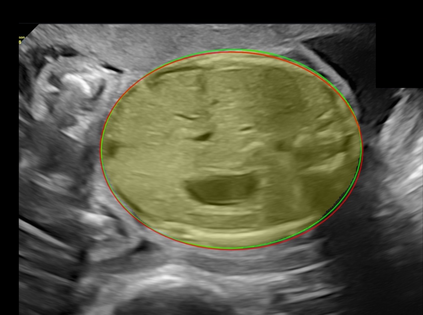

In this paper, we propose an end-to-end multi-task neural network called FetalNet with an attention mechanism and stacked module for spatio-temporal fetal ultrasound scan video analysis. Fetal biometric measurement is a standard examination during pregnancy used for the fetus growth monitoring and estimation of gestational age and fetal weight. The main goal in fetal ultrasound scan video analysis is to find proper standard planes to measure the fetal head, abdomen and femur. Due to natural high speckle noise and shadows in ultrasound data, medical expertise and sonographic experience are required to find the appropriate acquisition plane and perform accurate measurements of the fetus. In addition, existing computer-aided methods for fetal US biometric measurement address only one single image frame without considering temporal features. To address these shortcomings, we propose an end-to-end multi-task neural network for spatio-temporal ultrasound scan video analysis to simultaneously localize, classify and measure the fetal body parts. We propose a new encoder-decoder segmentation architecture that incorporates a classification branch. Additionally, we employ an attention mechanism with a stacked module to learn salient maps to suppress irrelevant US regions and efficient scan plane localization. We trained on the fetal ultrasound video comes from routine examinations of 700 different patients. Our method called FetalNet outperforms existing state-of-the-art methods in both classification and segmentation in fetal ultrasound video recordings.